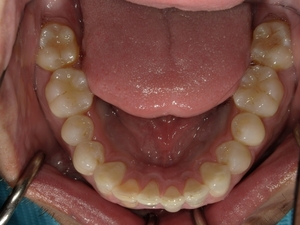

ガタガタとした歯並びや八重歯(叢生)CASE74